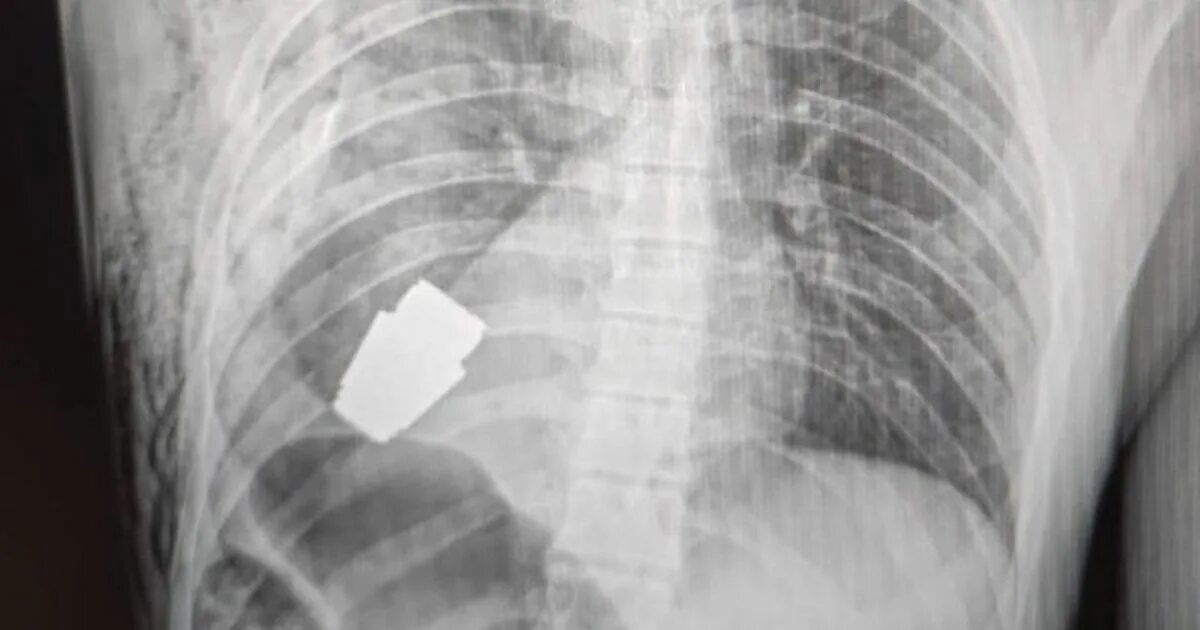

Операция опасно или нет